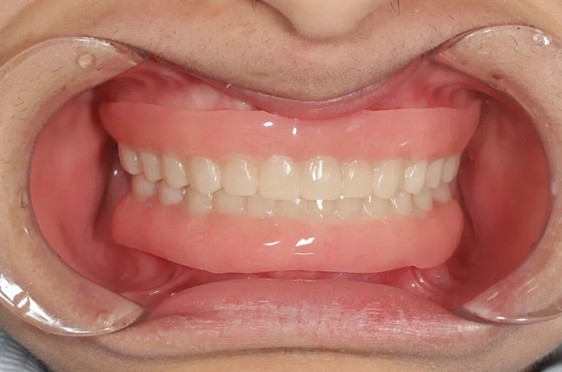

第四步,精细调。团队以微米级精度逐点检查咬合关系,边缘打磨至光滑。整个过程耗时数小时,仅调环节就反复验证数十次。

完成树脂冠咬合重建后,小文的面下1/3高度得到恢复,咬合功能重建完成。但张静亚医生明确表示:当前方案属于过渡性修复。

两年后待小文成年,将评估颌骨发育状况,决定是否更换为全瓷冠等永久性修复体。若骨量条件改善,可进一步考虑种植牙。